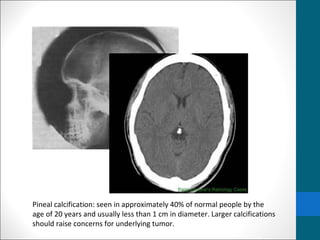

Pineal calcification: seen in approximately 40% of normal people by the

age of 20 years and usually less than 1 cm in diameter. Larger calcifications

should raise concerns for underlying tumor.

Pineal calcification: seenin approximately 40% of normal people by the age of 20 years and usually less than 1 cm in diameter. Larger calcifications should raise concerns for underlying tumor.